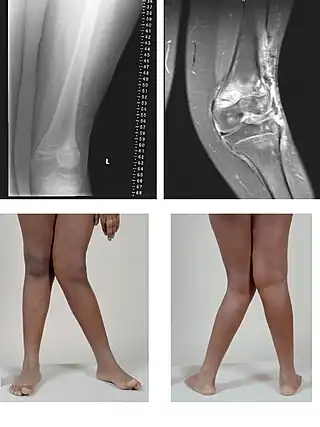

Rotura de los ligamentos cruzados

La rotura del ligamento cruzado anterior es una lesión frecuente. Puede producirse durante la actividad deportiva por giros enérgicos de la rodilla en los que el pie permanece en fuerte contacto con el suelo. El mecanismo lesional suele asociarse a semiflexión, valgo y rotación externa de la articulación de la rodilla. En el momento en que se sufre esta lesión suele sentirse un dolor intenso y una sensación de chasquido. En condiciones normales el ligamento cruzado anterior sirve de freno para evitar un movimiento anterior excesivo de la tibia con respecto al fémur. El médico puede realizar pruebas exploratorias como la Prueba del cajón y la Prueba de Lachman que si son positivas hacen más probable este diagnóstico. Su confirmación se obtiene mediante la resonancia magnética o artroscopia.[23] En la lesión combinada, conocida como triada de O'Donoghue o rodilla desgraciada, se suman la rotura del ligamento cruzado anterior, del ligamento lateral interno y del menisco interno.[24]

Rotura de meniscos

El menisco se lesiona generalmente por un mecanismo de rotación, cuando la rodilla se encuentra en situación de semiflexión y con el pie apoyado. En estas circunstancias, al producirse la rotación, el cóndilo del fémur presiona directamente al menisco y este se rompe o fisura. Esta lesión afecta con mayor frecuencia al menisco interno o medial que al externo. Las roturas pueden llegar a ser de una gravedad significativa. Se dividen en horizontales, verticales, transversales, oblicuas o mixtas. El diagnóstico se basa en la presencia de síntomas y signos clínicos característicos, en los hallazgos reportados por la resonancia magnética y artroscopia. Esta última puede ser al mismo tiempo diagnóstica y terapéutica.[20]